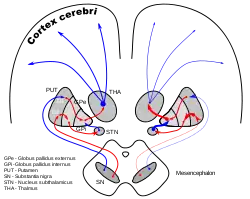

Dopamine-loops in Parkinson's disease | |

The globus pallidus (GP), also known as paleostriatum or dorsal pallidum,[1] is a subcortical structure of the brain. It consists of two adjacent segments, one external, known in rodents simply as the globus pallidus, and one internal, known in rodents as the entopeduncular nucleus. It is part of the telencephalon, but retains close functional ties with the subthalamus in the diencephalon – both of which are part of the extrapyramidal motor system.[2] The globus pallidus is a major component of the basal ganglia, with principal inputs from the striatum, and principal direct outputs to the thalamus and the substantia nigra. The latter is made up of similar neuronal elements, has similar afferents from the striatum, similar projections to the thalamus, and has a similar synaptology. Neither receives direct cortical afferents, and both receive substantial additional inputs from the intralaminar thalamus.

The two parts receive successively a large quantity of GABAergic axonal terminal arborisations from the striatum through the dense striato-pallidonigral bundle. The synaptology is very peculiar (see primate basal ganglia system).[5][6] The striatal afferents contribute more than 90% of synapses. The two pallidal nuclei receive dopaminergic axons from the pars compacta of the substantia nigra.

ROSTRAL: striatum, globus pallidus (GPe and GPi)

CAUDAL: subthalamic nucleus (STN), substantia nigra (SN)

Pathway

This area of the basal ganglia receives input from another area, called the striatum, which has two parts, the caudate nucleus and the putamen. This data is routed to the thalamus, either directly or indirectly. In the case of the interna, one area of the globus pallidus, the structure can feed directly to the thalamus. The externa, which lies on the outside of this structure, feeds information to the interna, where it can be passed on to the thalamus.